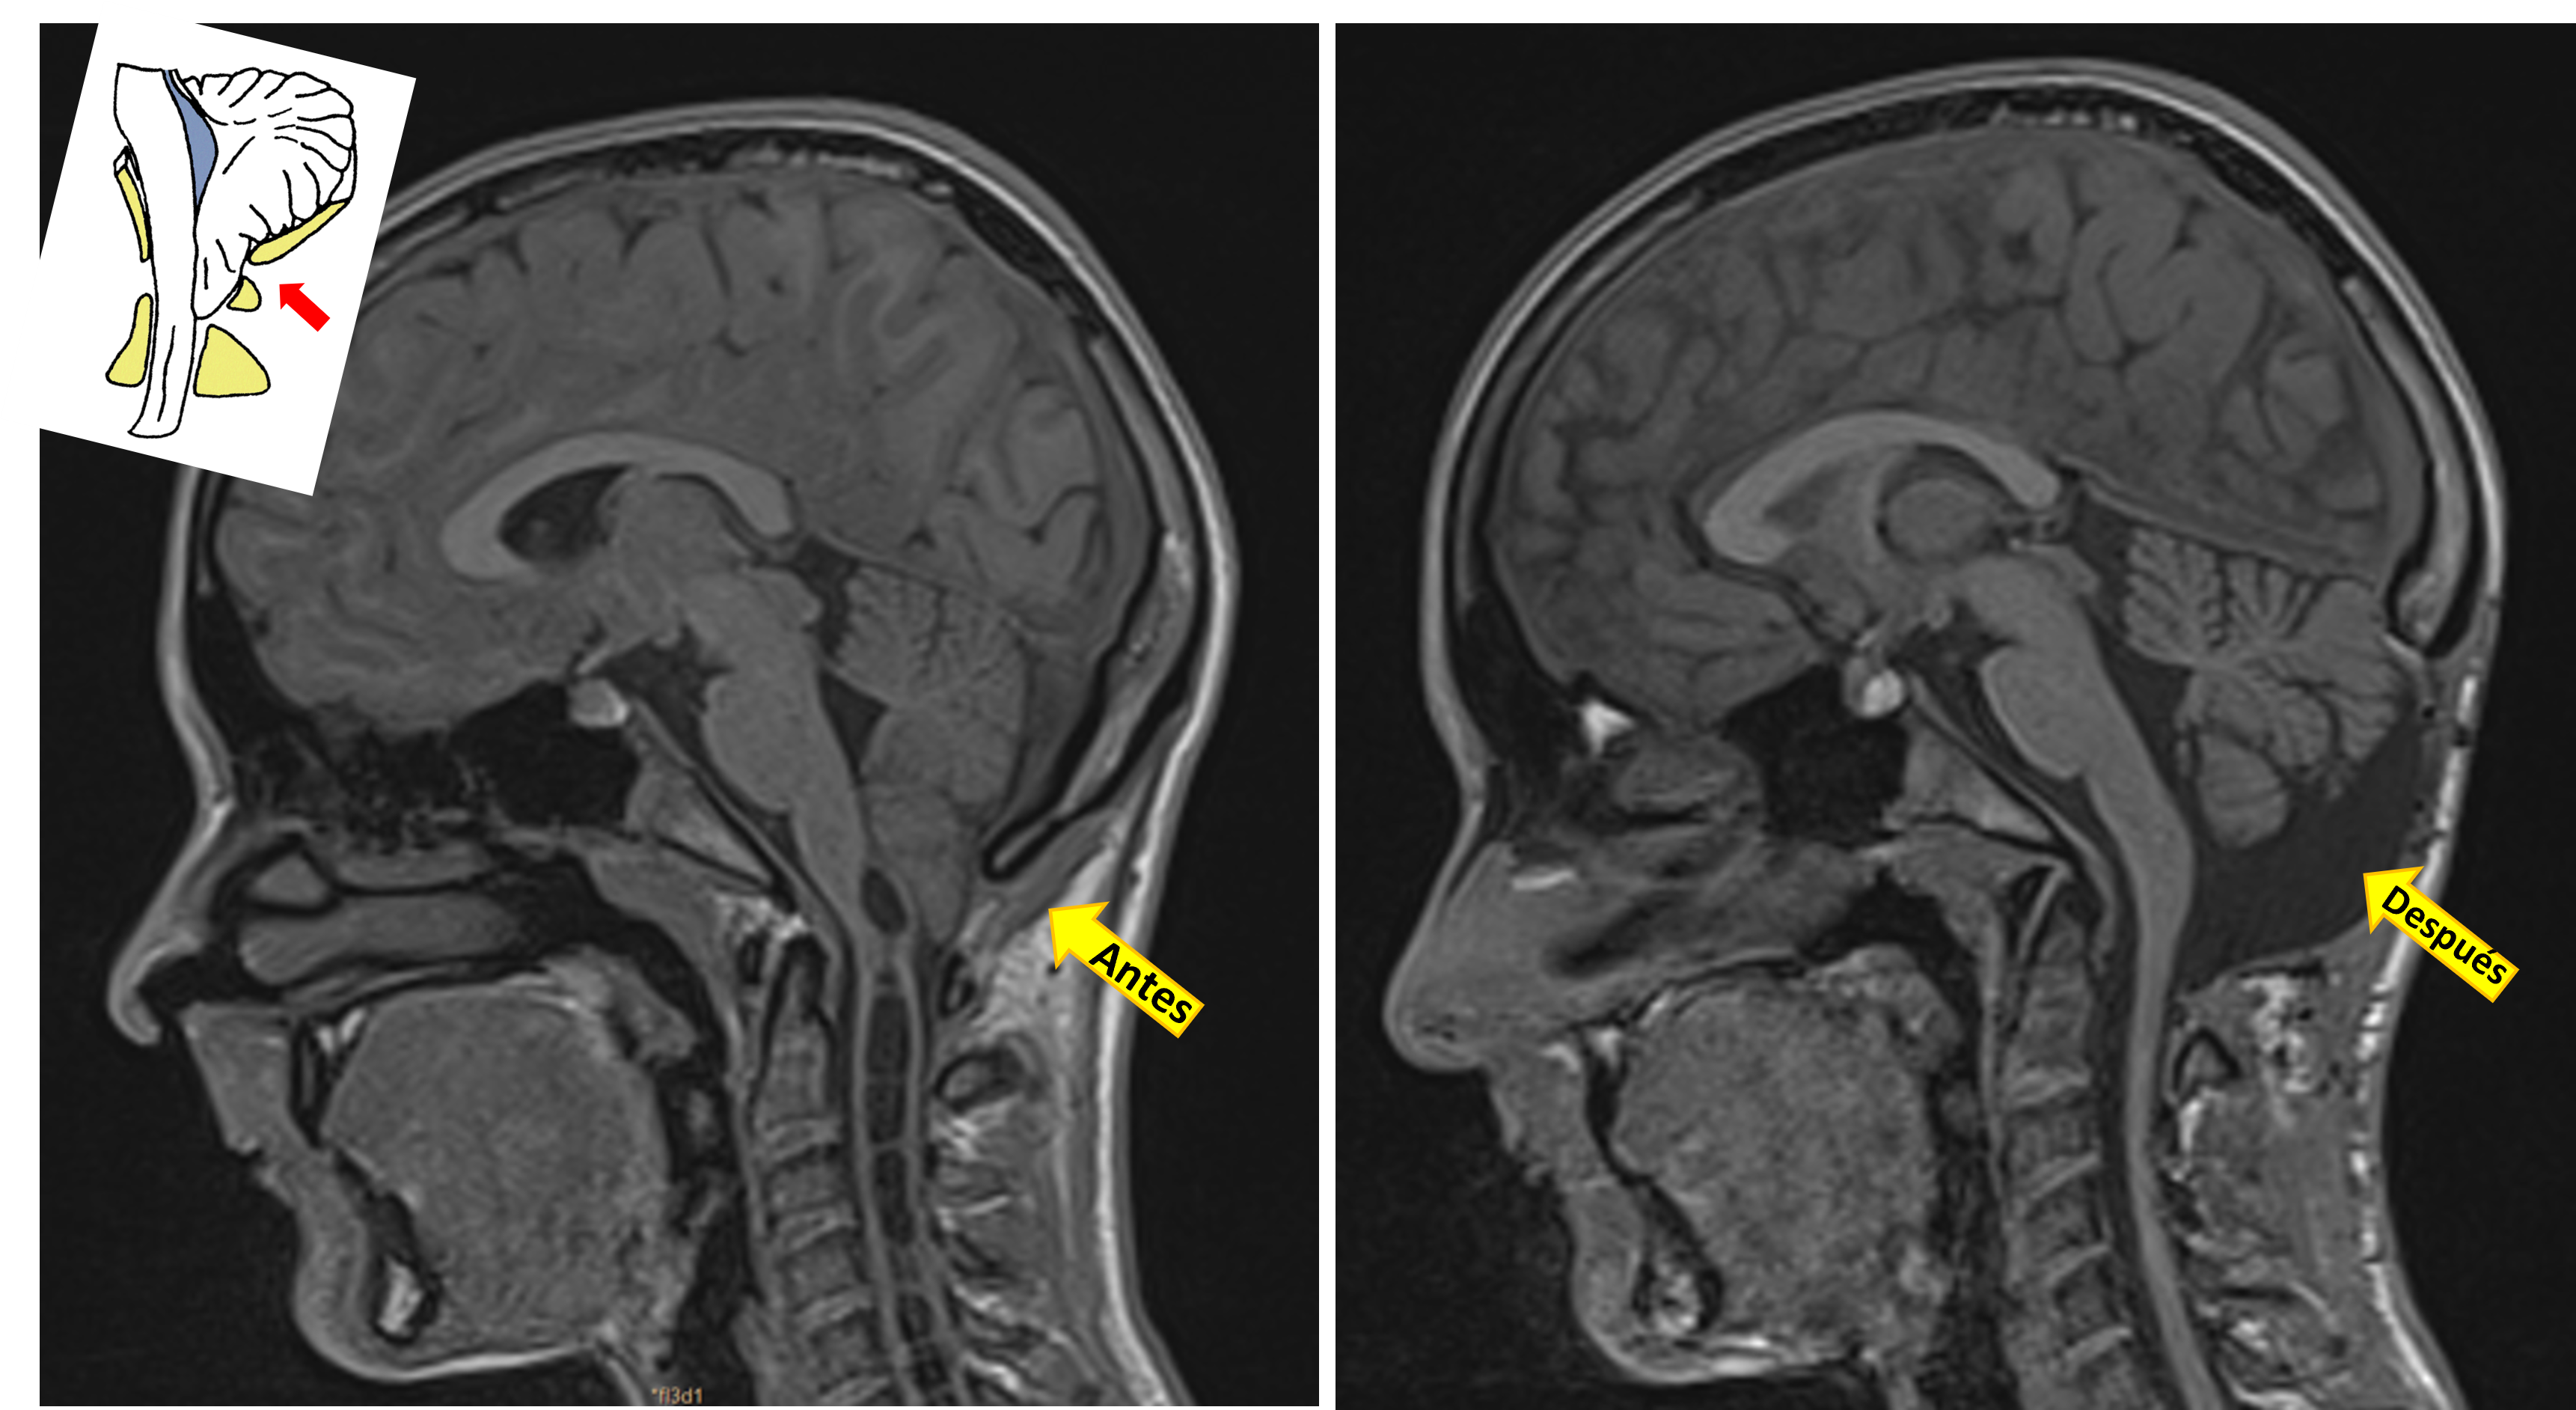

Lineas investigación Chiari